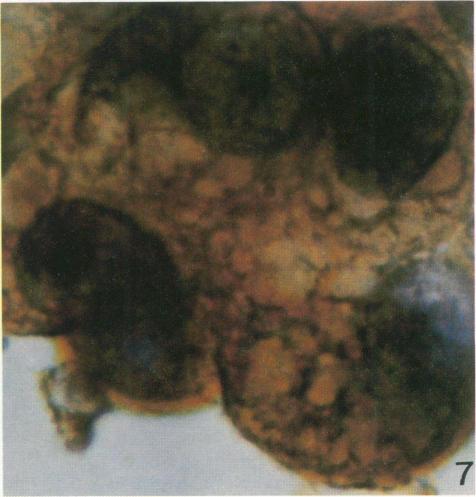

An immunoperoxidase technique employing antibody to prekeratin was used to study distribution and pattern of staining of prekeratin filaments in cytological smears obtained from 42 specimens of pleural and peritoneal effusions (27 benign, 15 malignant). The smears were either air-dried or ethanol-fixed. Both benign and malignant mesothelial cells showed distinctive peripheral or perinuclear staining patterns which differed from the characteristic arborizing pattern in adenocarcinoma cells. The ultrastructure of these 2 cell types studied in 27 body fluids (12 benign, 15 malignant) and in 13 malignant tumors (3 mesotheliomas, 10 adenocarcinomas) showed a distinctive localizaton of intermediate filaments which corresponded to and could explain the pattern of staining obtained using the immunoperoxidase technique. The immunohistochemical and ultrastructural findings appeared characteristic for benign and malignant mesothelial cells as well as for adenocarcinoma cells, and could be used as markers to differentiate mesothelial tumors and reactive mesothelial cells from adenocarcinomas.

采用抗前角蛋白抗体的免疫过氧化物酶技术,研究了取自42例胸腔和腹腔积液标本(27例良性,15例恶性)的细胞学涂片上前角蛋白丝的分布和染色模式。涂片采用空气干燥或乙醇固定。良性和恶性间皮细胞均显示出独特的周边或核周染色模式,这与腺癌细胞中典型的树枝状模式不同。在27份体液(12份良性,15份恶性)和13例恶性肿瘤(3例间皮瘤,10例腺癌)中研究的这两种细胞类型的超微结构显示,中间丝有独特的定位,这与免疫过氧化物酶技术获得的染色模式相符且可以解释该模式。免疫组织化学和超微结构研究结果对于良性和恶性间皮细胞以及腺癌细胞而言似乎具有特征性,并且可以用作将间皮肿瘤和反应性间皮细胞与腺癌区分开来的标志物。